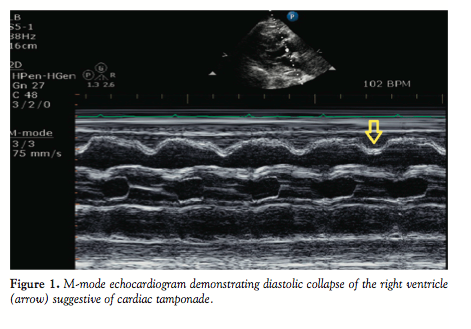

During her current admission, she developed refractory shock. Cardiac biomarkers became positive, with a peak troponin-I of 24.6 ng/mL in 24 hours (99th centile <0.08 ng/mL). ECG

demonstrated low QRS voltage, but was otherwise unremarkable. Physical examination showed a 35 mm Hg pulsus paradox. Bedside echocardiogram revealed a large anterior pericardial effusion with late diastolic collapse of the right ventricle suggestive of cardiac tamponade (Figure 1). There were no wall-motion abnormalities seen and the ASD device was intact. The patient was taken emergently to the catheterization lab, where cardiac tamponade was confirmed and pericardiocentesis was performed with evacuation of 100 cc of serous fluid. Coronary angiography was unremarkable for obstructive coronary disease. Pericardial fluid analysis was unrevealing, with a white cell count of 6375 cells/mm3 (1% eosinophils). All microbiological culture data remained negative. Despite successful pericardiocentesis, her clinical course remained unfavorable. Over the next 48 hours, she developed progressive multi-organ dysfunction requiring high-dose vasopressors, mechanical ventilation, and renal replacement therapy. A right heart catheterization was repeated (Table 1), showing elevated right-sided filling pressures. Repeat echocardiogram did not show reaccumulation of pericardial fluid and a concern for a restrictive cardiomyopathy was raised. Heart failure service was consulted for possibility of heart transplantation. Pathological and laboratory work-ups for restrictive cardiomyopathy were unrevealing.